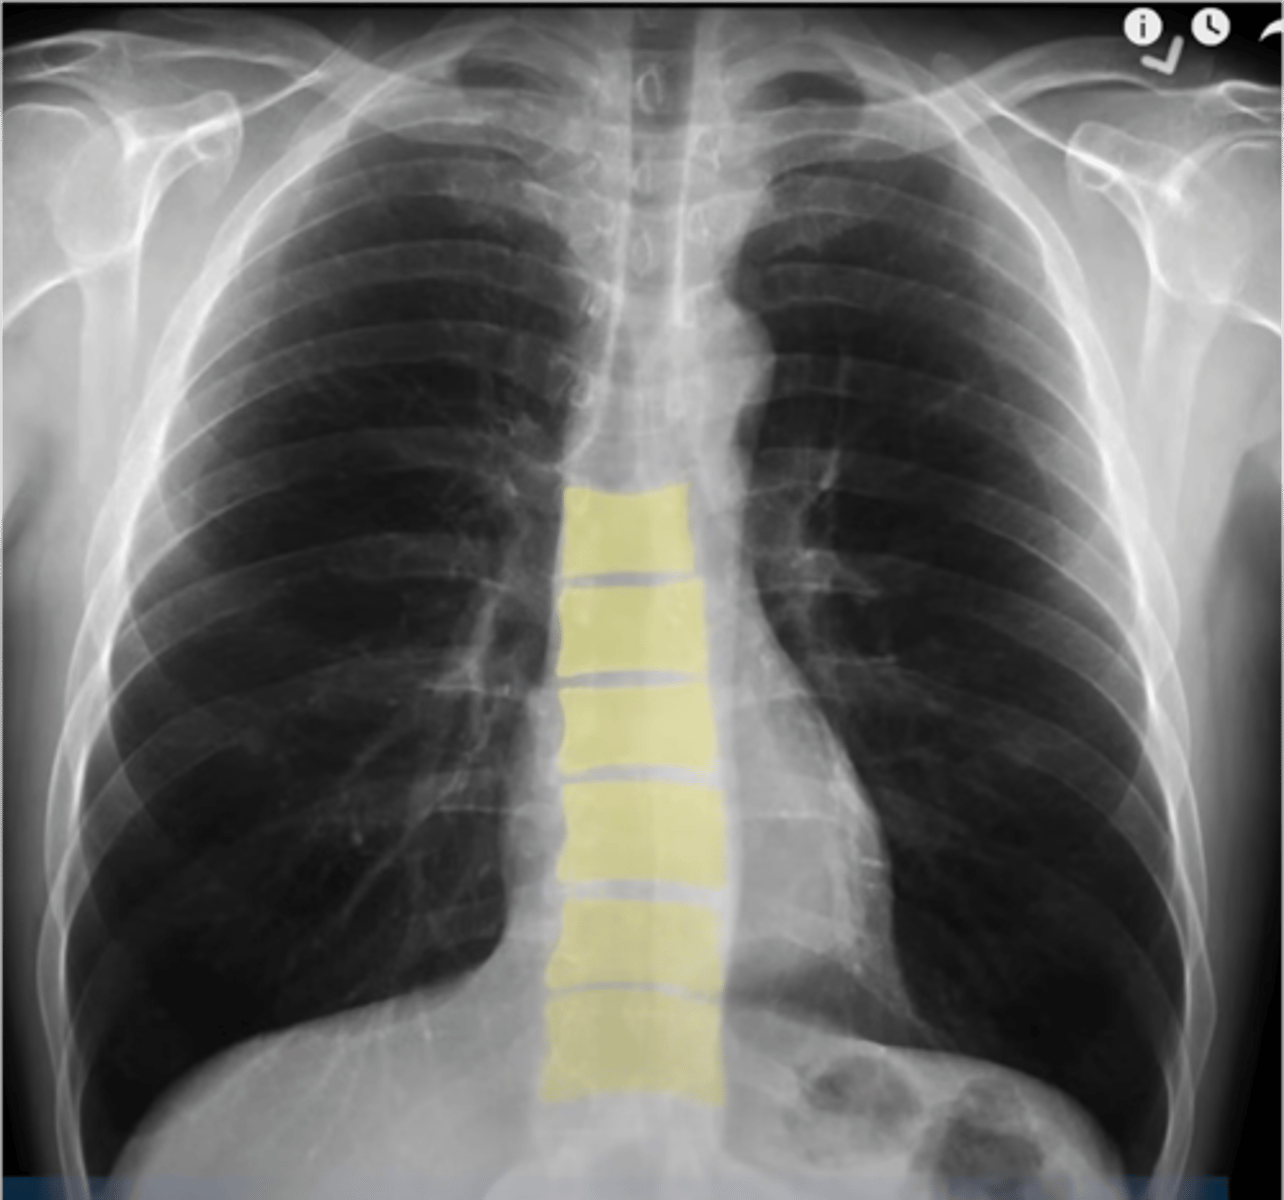

-exposure: can the details be seen (ex. the vertebral bodies behind the heart)

what does the E stand for in RIPE

-excess brightness: falsely prominent pulm markings

-diminished brightness: falsely diminished pulm markings

-excess or diminshed contrast: falsely diminished pulm markings (obscurs pulm nodules or pneumothoraces)

what are the consequences of inadequate exposure and penetration?